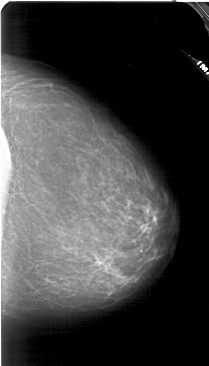

A_1880_1.RIGHT_MLO

RIGHT_CC LINES 4756 PIXELS_PER_LINE 2716 BITS_PER_PIXEL 12 RESOLUTION 43.5 NON_OVERLAY